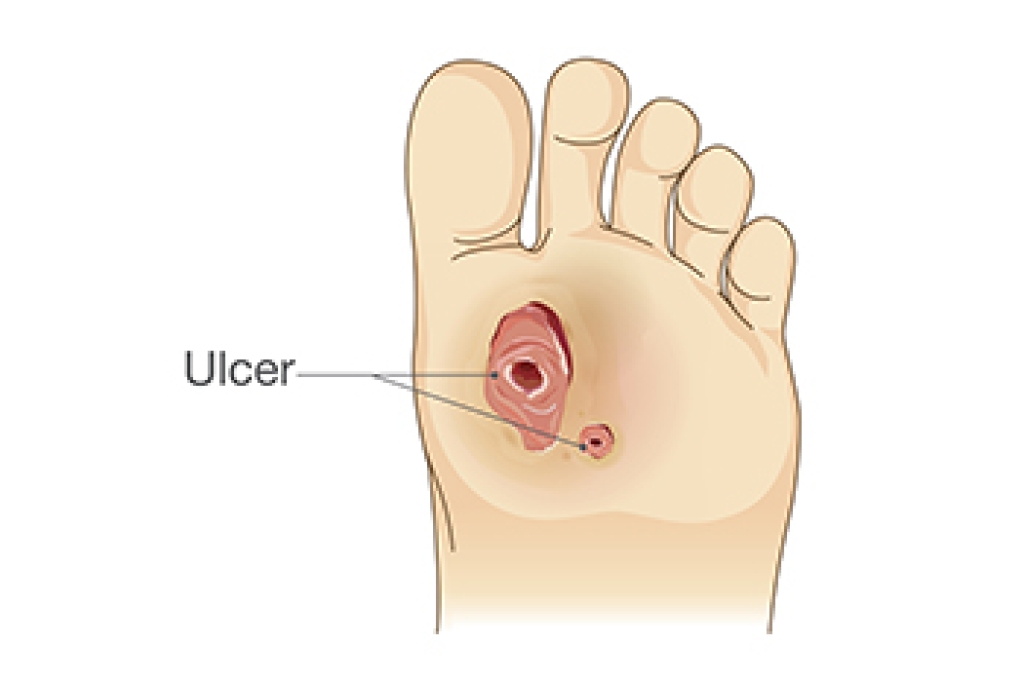

Pressure Sores Can Lead to Foot Ulcers

Rubbing points, also termed pressure sores, on the feet, toes, or ankles can progress into serious foot ulcers if left untreated. These pressure sores develop when prolonged pressure reduces blood flow, damaging the skin and underlying tissues. People with health conditions that impair circulation, such as diabetes or vascular disease, face a higher risk. Pressure sores are classified by severity, starting as red, painful skin and potentially worsening into deep wounds that expose muscle or bone. Common rubbing sites include the heels and bony areas of the foot. Without proper care, these wounds may become infected, further complicating healing. A podiatrist can assess the severity of a pressure sore and recommend appropriate treatment to prevent complications. This may involve wound care, pressure relief strategies, specialized dressings, or in severe cases, surgery to remove damaged tissue. Regular monitoring and professional treatment are essential to reduce the risk of infection and promote healing. If you have foot sores that are not healing properly, it is suggested that you schedule an appointment with a podiatrist for wound care treatment.

What Is Wound Care?

Wound care is the practice of taking proper care of a wound. This can range from the smallest to the largest of wounds. While everyone can benefit from proper wound care, it is much more important for diabetics. Diabetics often suffer from poor blood circulation which causes wounds to heal much slower than they would in a non-diabetic.

What Is the Importance of Wound Care?

While it may not seem apparent with small ulcers on the foot, for diabetics, any size ulcer can become infected. Diabetics often also suffer from neuropathy, or nerve loss. This means they might not even feel when they have an ulcer on their foot. If the wound becomes severely infected, amputation may be necessary. Therefore, it is of the upmost importance to properly care for any and all foot wounds.

How to Care for Wounds

The best way to care for foot wounds is to prevent them. For diabetics, this means daily inspections of the feet for any signs of abnormalities or ulcers. It is also recommended to see a podiatrist several times a year for a foot inspection. If you do have an ulcer, run the wound under water to clear dirt from the wound; then apply antibiotic ointment to the wound and cover with a bandage. Bandages should be changed daily and keeping pressure off the wound is smart. It is advised to see a podiatrist, who can keep an eye on it.